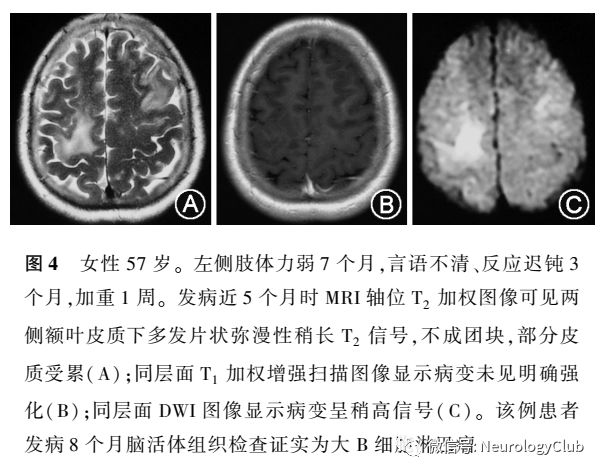

PCNSL临床上常呈慢性或亚急性起病,一般发病在50岁以上,男女均可发病,后期进展较快,临床上多以反应迟钝、认知障碍及精神症候为主,容易被误诊为脑梗死或病毒性脑炎等病变以中线及旁中线结构脑实质最易受累,多以基底节、丘脑、脑干、脑室旁为中心,可有占位效应,也可在皮质下白质区呈斑片状浸润性生长,极少数PCNSL可单独侵犯脑膜或神经根,或在海绵窦附近生长。脊髓的PCNSL很少,我们所见的1例脊髓PCNSL考虑还是由脑部向下播散种植而来,而非原发于脊髓。脑平扫CT可呈低、等或高密度信号MRI可见稍长T1、稍长T2信号,DWI呈稍高信号,少见出血信号。CT或MRI增强后多呈均一团块、结节或云雾状强化。有的PCNSL表现形式特殊,脑MRI示双侧大脑半球弥漫性病变,但无明显的团块病变,类似于白质脑病样改变,早期可无强化,也容易与GC相混淆临床上多以反应迟钝、记忆力下降等认知障碍起病为主要表现,早期脑活检也不容易诊断(尤其是应用小剂量糖皮质激素治疗后),有的病理学表现为脑白质内弥漫的淋巴细胞浸润,无明确肿块形成,这是大脑淋巴瘤病(lymphomatosis cerebri)的特点,我们所诊治的1例57岁女性患者,因左侧肢体力弱7个月,言语不清、反应迟钝3个月,在多家医院分别按脑梗死、病毒性脑炎、脱髓鞘病等治疗效果不明显,临床影像表现符合大脑淋巴瘤病的特点(图4),最后,由本院确诊。因此,我们必须了解大脑淋巴瘤病的概念及临床影像特点,注意在实践中进行诊断与鉴别诊断。